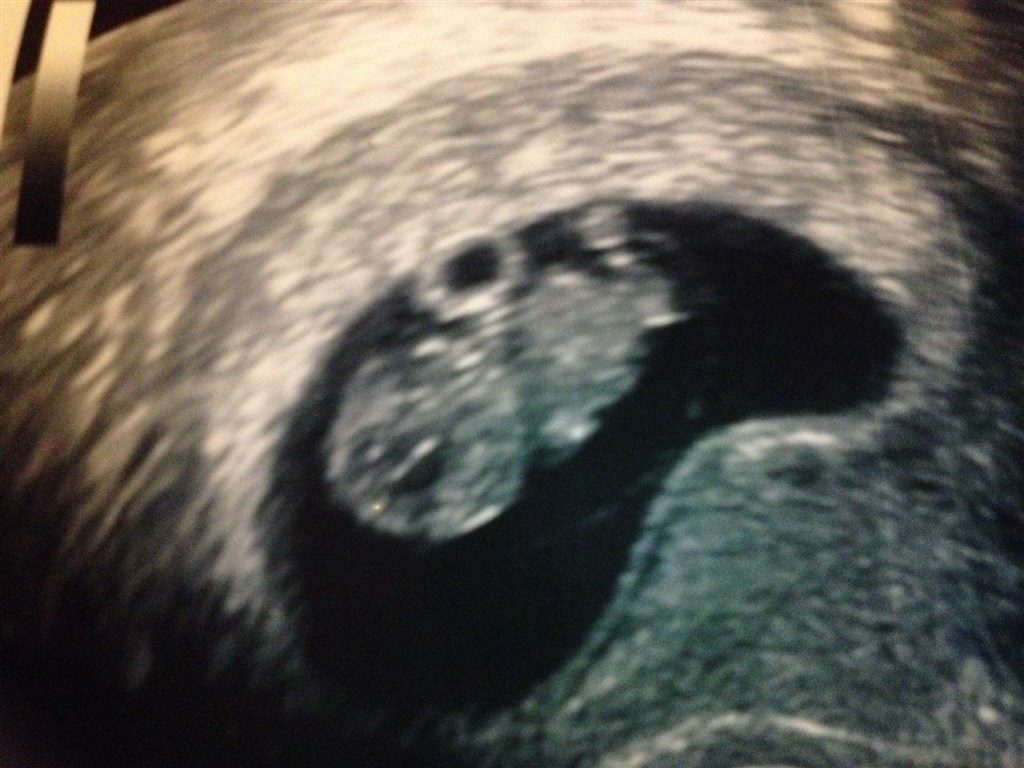

Sådan, tror jeg har fået dem med nu ..

Den ville simpelthen ikke ligge dem ind fra mobilen i dag, fjollet!

Vedhæftede fotos (klik for at se i fuld størrelse)

Her får du lige billede fra vores første og anden scanning. Uge 7+2 og 8+2

der sker så meget på en uge